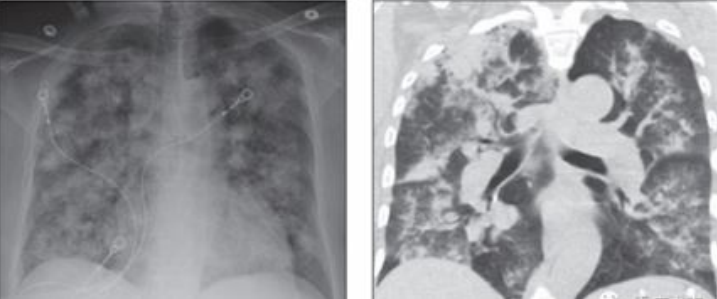

20岁男性患者,肾衰竭,咯血,血红蛋白5.3 g/dl。胸部CT提示弥漫性非特异性磨玻璃影,融合区域(箭头)和双侧多个亚厘米结节影。

61岁女性患者,抗中性粒细胞胞质抗体相关性血管炎,表现为呼吸困难和低氧血症;胸部X线片显示双侧多发致密结节和斑片状实变高密度影,提示弥漫性肺疾病;CT显示相应的弥漫性结节性和轮廓不清的实变影。

72岁女性患者,肉芽肿性多血管炎,表现为呼吸困难。胸部X线片显示左中肺有密集的局灶性肺高密度影;右肺可见近端支气管(箭头)壁增厚和扩张;CT提示左上叶实变影,病灶周围磨玻璃影。

51岁男性患者,体重减轻,慢性咯血,抗中性粒细胞胞质抗体阴性,活检显示含铁血黄素沉着。